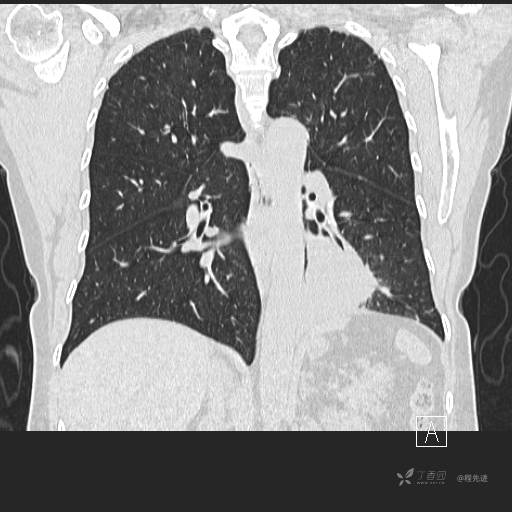

冠状位重建

CT值:平扫:31HU,动脉期:74HU,静脉期:84HU